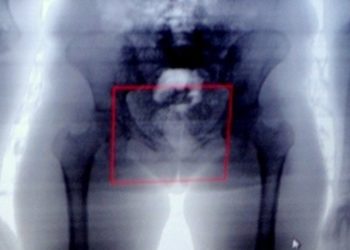

Cinco mulheres são flagradas quando tentavam entrar em presídio com drogas nas partes íntimas

Flagrantes através do Body Scanner aconteceram em Feira de Santana